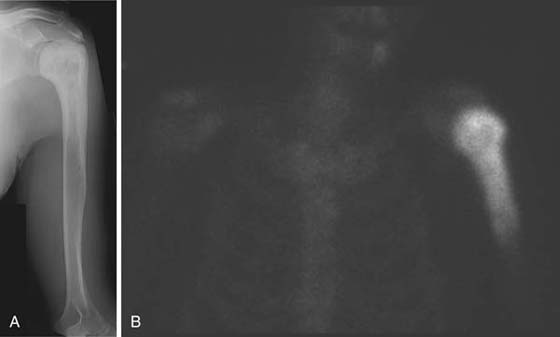

Nuclear Medicine

In nuclear medicine a radiopharmaceutical (radioactive isotope coupled with a pharmaceutical) is administered (usually intravenously), and subsequent gamma ray emissions are detected by a gamma camera. An isotope whole-body bone scan is used to detect areas of increased bone turnover, which may indicate pathology depending on the site and degree of activity (Fig. 14-5). The main application in the shoulder and elbow is in the evaluation of neoplasia (particularly to assess for metastatic disease) and osteomyelitis.13

images

Figure 14-5 Paget’s disease. A, Anteroposterior radiograph of the left humerus demonstrates bony expansion and trabecular and cortical thickening proximally extending to the glenohumeral joint, consistent with Paget’s disease. B, Frontal image from an isotope whole-body bone scan shows marked tracer accumulation in the proximal humerus as expected in Paget’s disease.

The most significant recent advancement in nuclear medicine is positron emission tomography (PET) and combination PET CT scanners with important implications for oncology. (18F) fluorodeoxglucose (FDG) is a metabolic tracer most widely used in clinical PET oncology. PET applications are evolving, but it is currently approved for the diagnosis, staging, and restaging of many common malignancies and has shown efficacy for the detection of osseous metastasis from several malignancies, including lung carcinoma, breast carcinoma, and lymphoma.14 Such metastatic disease may be seen at the shoulder, but less commonly at the elbow and rarely more distally.